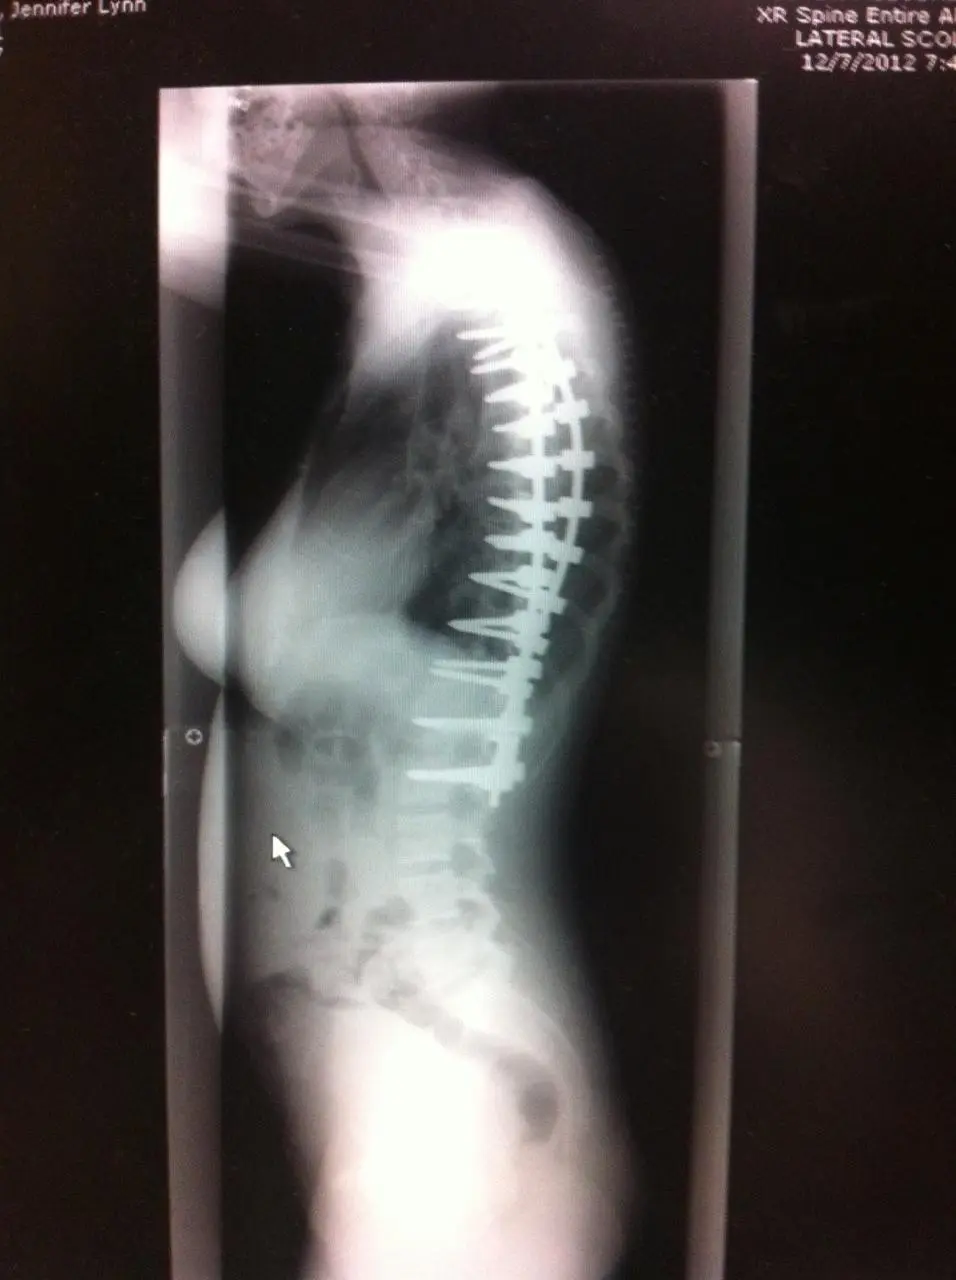

ทว่าสำหรับกรณีของหญิงสาวรายนี้อาการของโรคค่อนข้างแย่มากๆ เนื่องจากกระดูกสันหลังของเธอนั้นมีความคดของกระดูกสันหลังประมาณ 90 องศา และเธอจำเป็นต้องได้รับการผ่าตัดแก้ไขโดยแพทย์ผู้เชี่ยวชาญ และหลังจากที่แพทย์ได้ทำการผ่าตัดได้สำเร็จ ก็สามารถลดความโค้งของกระดูกสันหลังลดลงกว่า 20 องศา

สำหรับช่วงเวลาการพักฟื้นอาจใช้เวลาค่อนข้างนานพอสมควร เพราะผลจากการผ่าตัดอาจทำให้เกิดอาการปวดหลัง รวมไปถึงภาวะแทรกซ้อนอื่น ๆ แต่อย่างไรก็ตาม การผ่าตัดประเภทนี้ไม่เพียงแต่ดีต่อสุขภาพของผู้ป่วยในระยะยาวเท่านั้น แต่ยังช่วยยืดกระดูกสันหลังของผู้ป่วย ซึ่งจะทำให้พวกเขาดูสูงขึ้นอีกด้วย